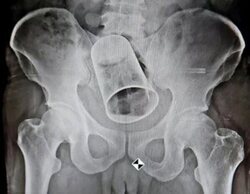

Operan a un hombre de 45 años por tener una copa metálica en el recto

El hombre tenía la copa metálica en el ano desde hacía 10 días pero le daba vergüenza acudir al médico.